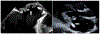

Results: Sixty-eight children met Duke criteria for infective endocarditis (43 definite and 25 possible). Twenty-three (34%) had identified neurologic complications, including intracranial haemorrhage (25%, 17/68) and ischaemic stroke (25%, 17/68). Neurologic symptoms began a median of 4.5 days after infective endocarditis symptom onset (interquartile range 1, 25 days), though five children were asymptomatic and diagnosed on screening neuroimaging only. Overall, only 56% (38/68) underwent neuroimaging during acute hospitalisation, so additional asymptomatic neurologic complications may have been missed. Children with identified neurologic complications compared to those without were older (48 versus 22% ≥ 13 years old, p = 0.031), more often had definite rather than possible infective endocarditis (96 versus 47%, p < 0.001), mobile vegetations >10mm (30 versus 11%, p = 0.048), and vegetations with the potential for systemic embolisation (65 versus 29%, p = 0.004). Six children died (9%), all of whom had neurologic complications.

Conclusions: Neurologic complications of infective endocarditis were common (34%) and associated with mortality. The true frequency of neurologic complications was likely higher because asymptomatic cases may have been missed without screening neuroimaging. Moving forward, we advocate that all children with infective endocarditis have neurologic consultation, examination, and screening neuroimaging. Additional prospective studies are needed to determine whether early identification of neurologic abnormalities may direct management and ultimately reduce neurologic morbidity and overall mortality.